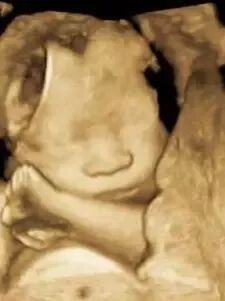

(普通三维彩超图)